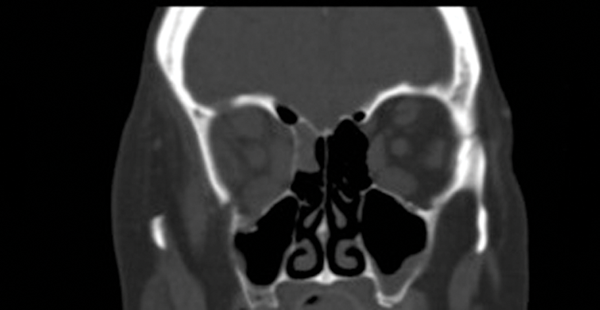

Figure 2: Two CT coronal images showing an interruption in the floor of her right orbit.

Note the enlarged extraocular muscles in thyroid eye disease.

An MRI scan was ordered to assess both soft tissue and orbital contour and confirmed an interruption to the floor of the right orbit.

Muscle was not trapped in the defect. There was no worsening of her previous diplopia and no infraorbital anaesthesia.